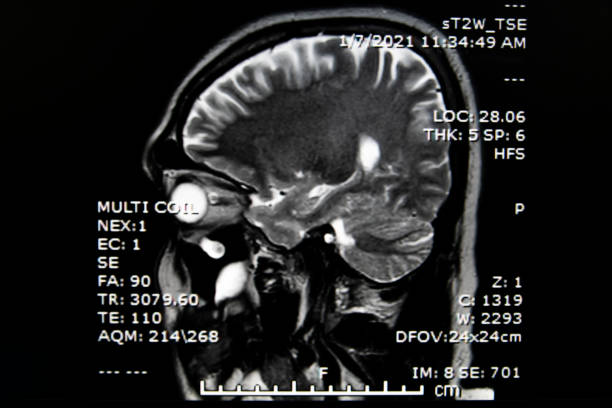

뇌경색 후유증은 심각한 장애를 남길 수 있는 신체적, 정신적 문제를 야기할 수 있는 중요한 주제입니다.

뇌경색 의심이 된다면 빠르게 대응해서 치료를 하는게 좋습니다.

뇌경색 후유증은 무시하면 평생 장애를 얻을 수 있는 매우 심각한 상태입니다.

따라서 뇌경색 후의 초기 징후를 무시하지 않고 즉각적인 의료 지원을 받는 것이 중요합니다.

초기 치료와 재활치료를 통해 후유증의 심각한 영향을 최소화할 수 있으며, 환자의 삶의 질을 개선할 수 있습니다.